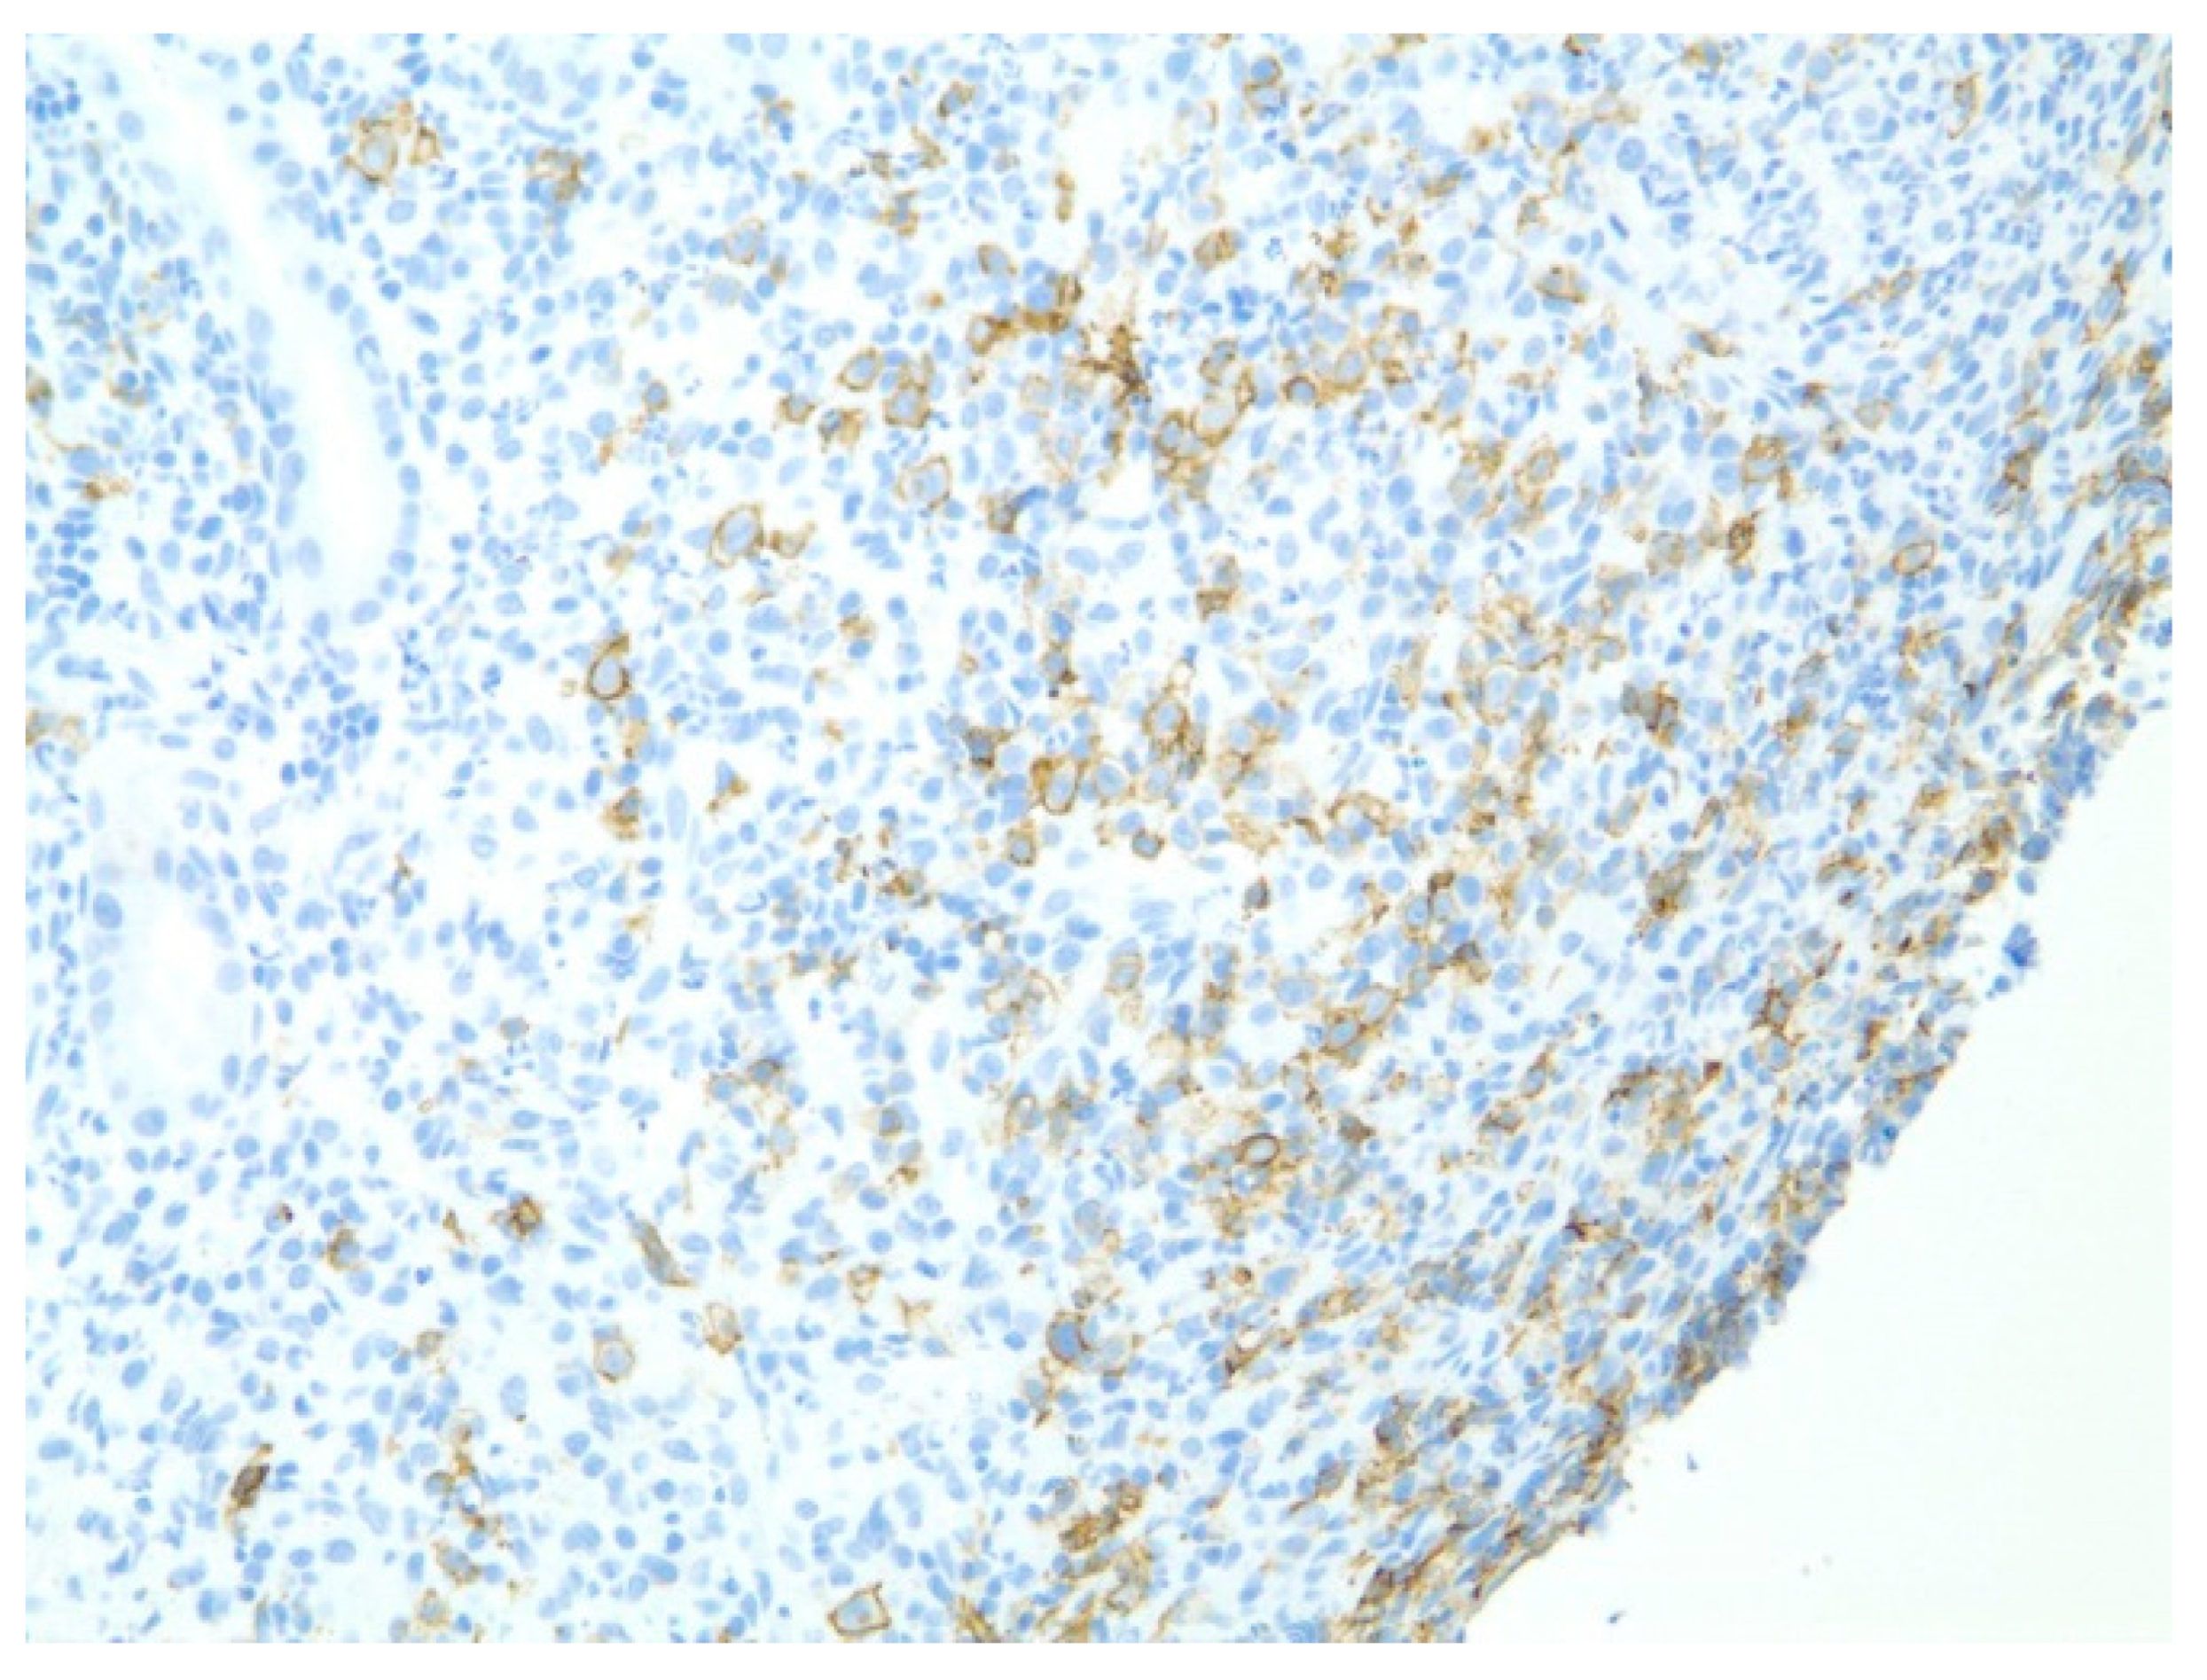

| 1 | F | 66 | Skin | Fundus, cardia, and body | Polypoid lesions with superficial ulcers | Esophagus, duodenum, mediastinum, cervical soft tissue, pancreas | Metastatic malignant melanoma | Radiotherapy and immunotherapy | Comfort care and death 5 days after EGD diagnosis of metastasis |